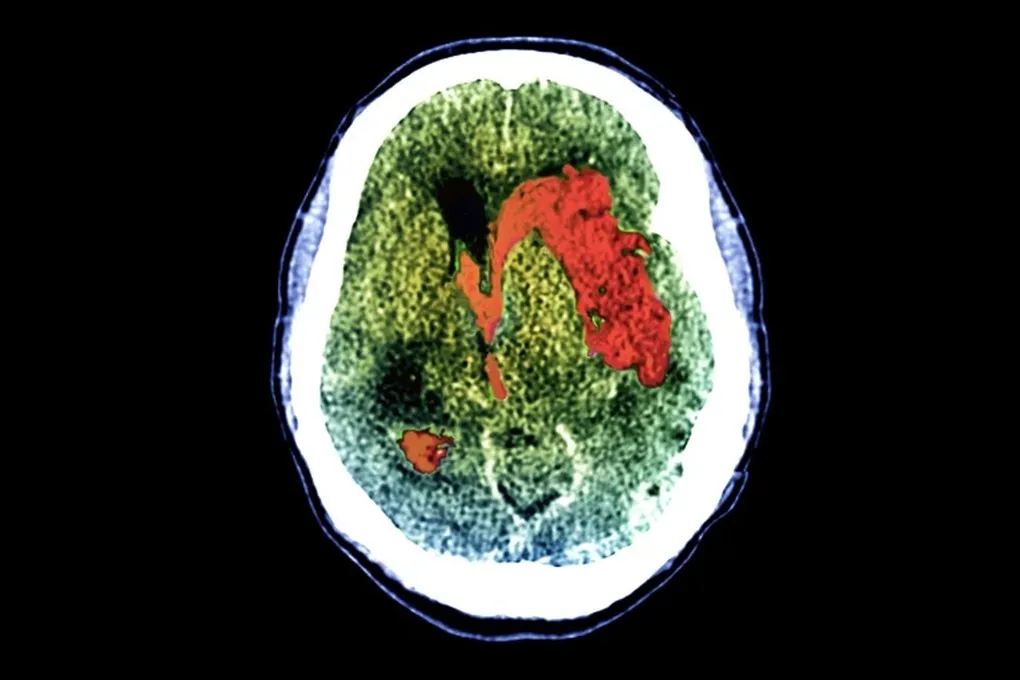

Сканирование мозга

Всем участникам провели фМРТ (измеряющую активность по кровотоку) или ЭЭГ (считывающую волны мозга электродами). Во время процедур их просили представить игру в теннис или сжатие руки. Мысленное, а не физическое. И вот что удивительно: среди тех, кто не пошевельнулся и мускулом, около 25% демонстрировали четкую мозговую активность в ответ на команды. Это явление назвали когнитивно-моторной диссоциацией — когда разум работает, а тело молчит.